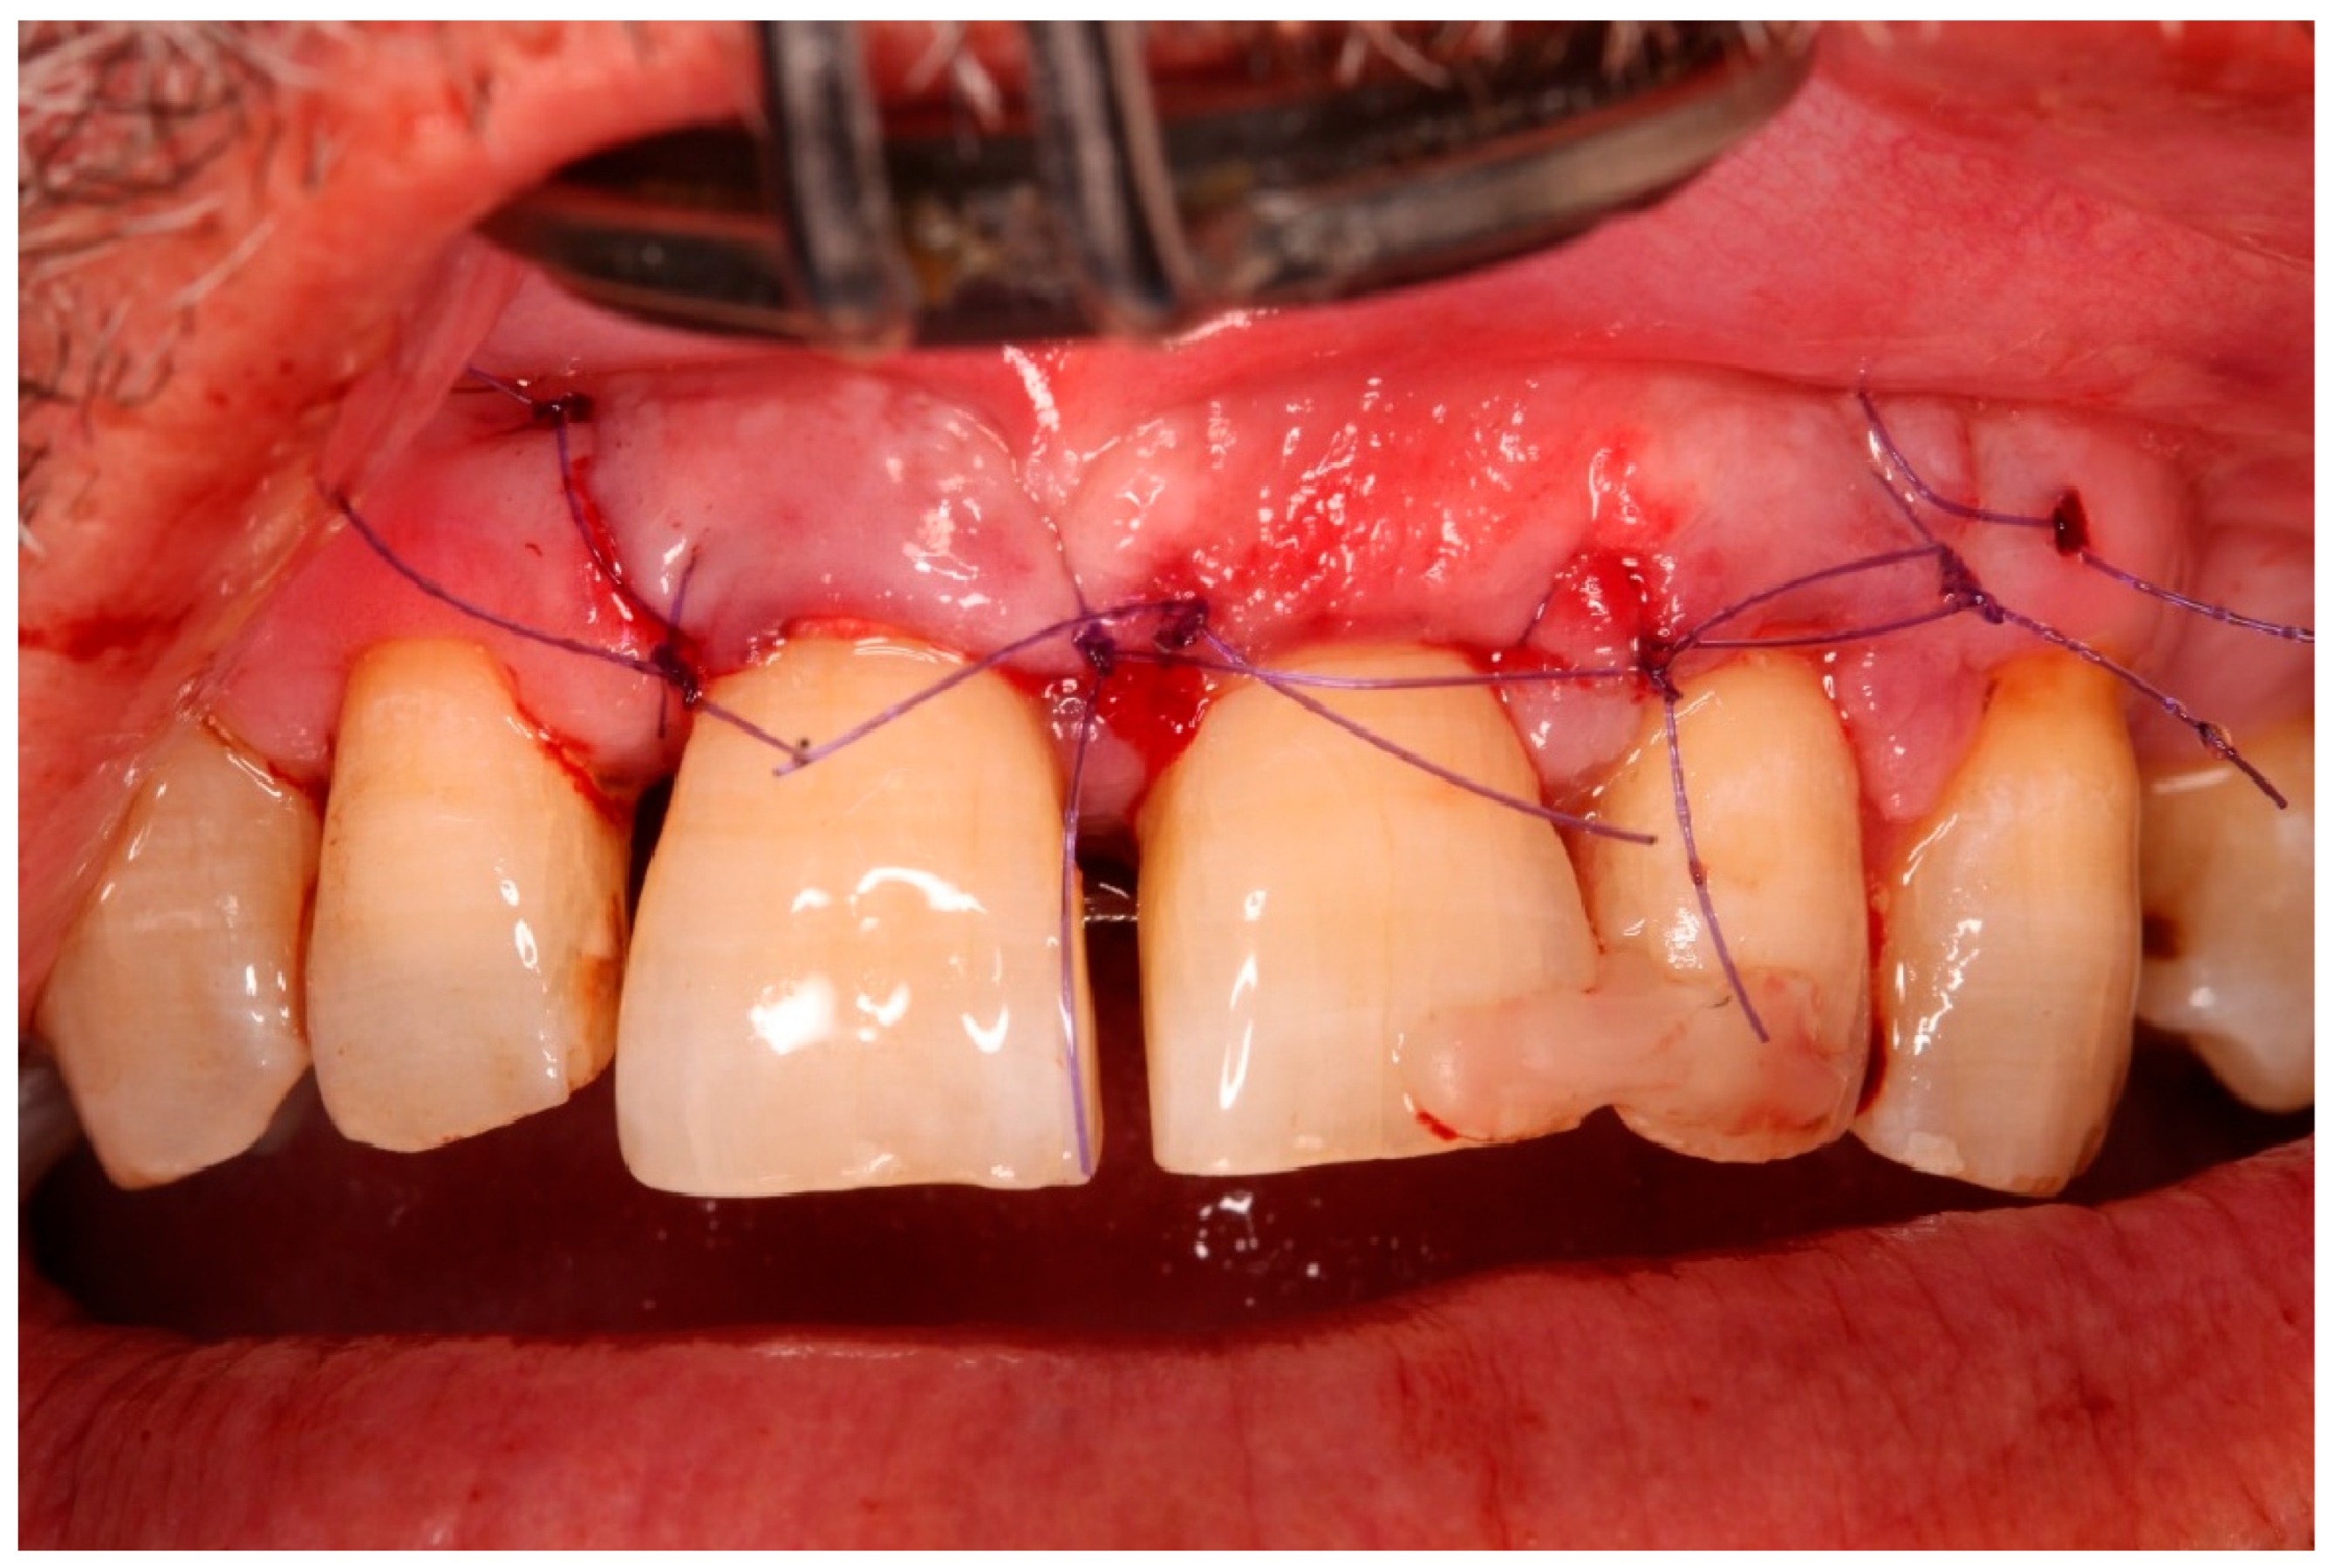

- Guided tissue regeneration: A full-thickness flap was elevated to expose the defect morphology. Autologous bone chips collected during drilling were combined with xenograft particles (Bio-Oss®, Geistlich Pharma, Wolhusen, Switzerland) and enamel matrix derivative (Emdogain®, Straumann, Basel, Switzerland) and placed around the replanted root. A resorbable collagen membrane (Bio-Gide®, Geistlich Pharma, Wolhusen, Switzerland) was positioned to stabilize the grafted area and support space maintenance. The flap was repositioned and sutured to achieve primary closure.

3.1. Clinical Findings

3.3. Functional and Aesthetic Outcomes